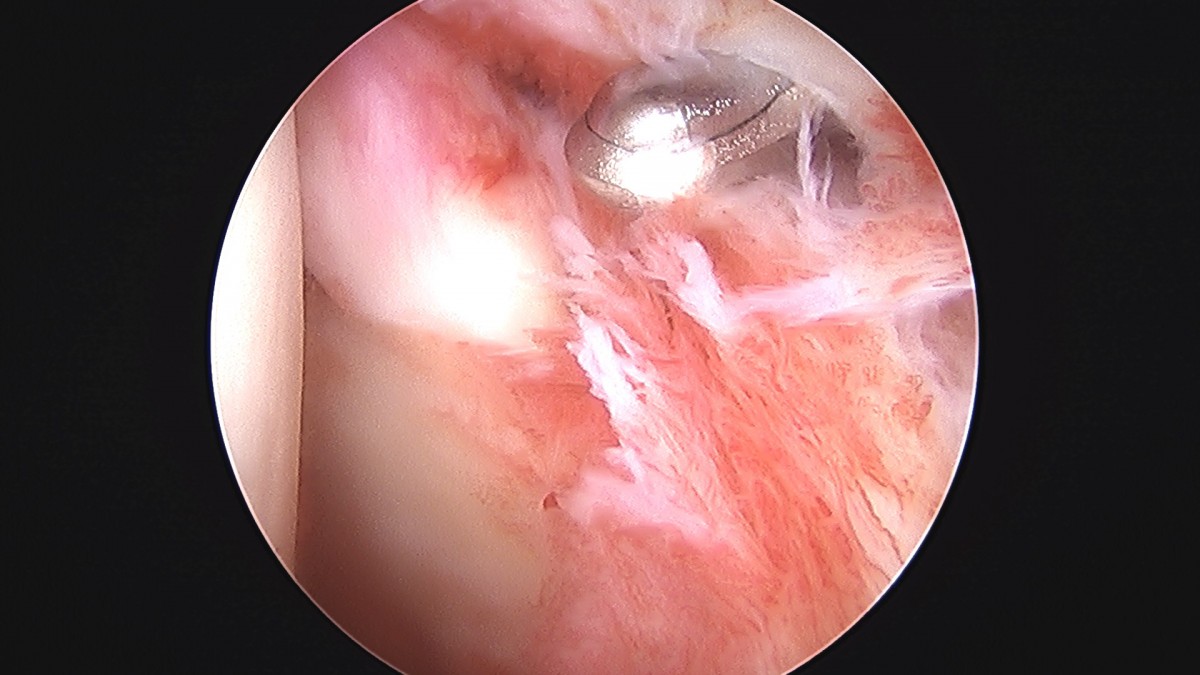

정지영원장님 어깨 관절낭 이완술 및 석회제거술 박설O 환자

작성자 최고관리자 댓글 0건 조회 732회 작성일 25-09-16 16:59